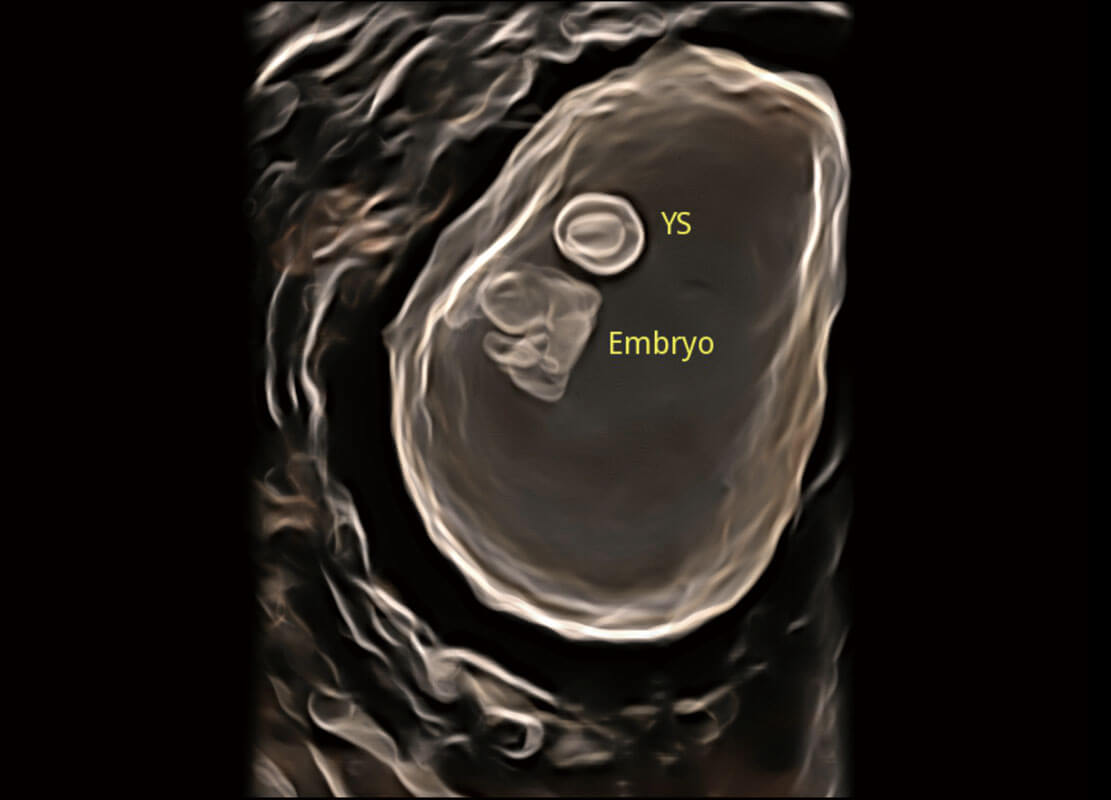

早孕筛查

P60在胎儿早孕期超声筛查中为您带来优异的图像质量。

• 早孕-胎心

• 高分辨率容积成像-早孕胎儿

• 胎儿体循环

• 光影成像-孕囊